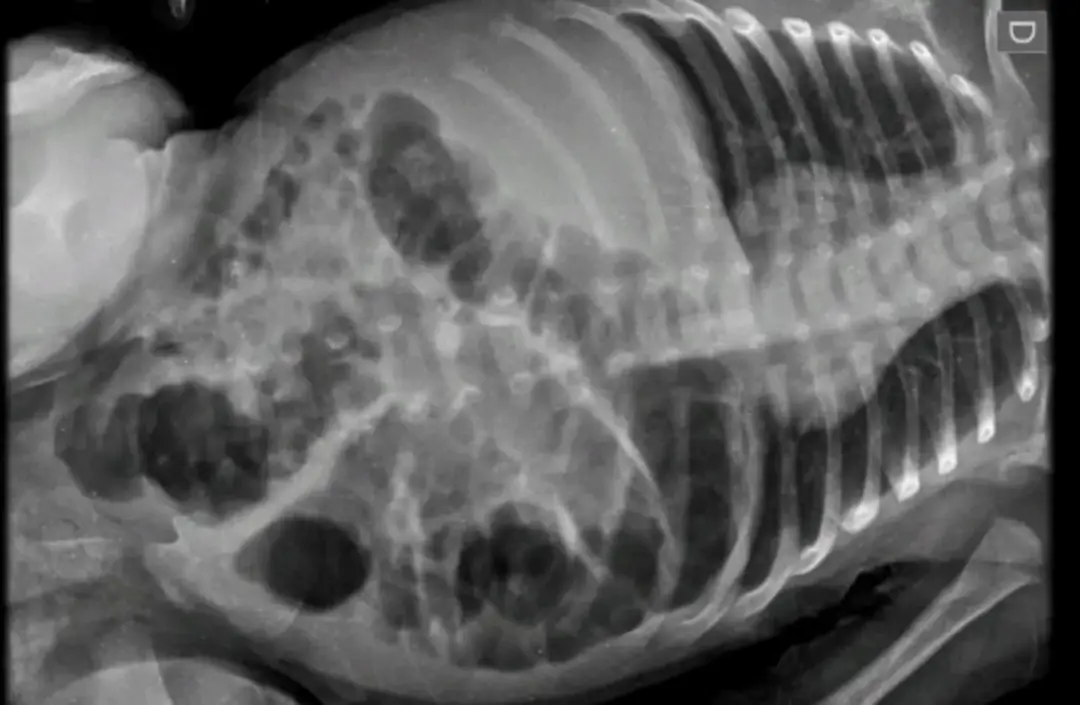

A criança sofreu lesões no rosto e barriga, além de fraturas na perna, antebraço e costelas. Segundo o delegado Rodrigo Baptista Santos, responsável pelo caso, as agravantes do crime são impossibilidade de defesa da vítima e crime praticado contra criança.

Diante do laudo do médico e do Instituto Médico Legal (IML), a Polícia Civil manteve o indiciamento. A criança sofreu ferimentos graves, se recupera bem e foi encaminhada pelo Conselho Tutelar para um abrigo do município, por determinação da Justiça.